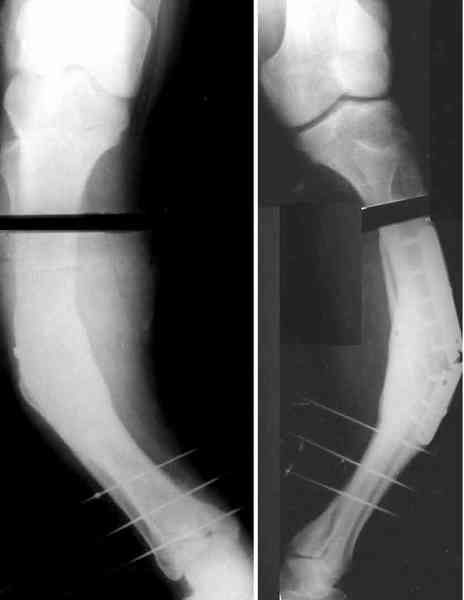

Для продолжения темы - несколько картинок.

Пациент 30 лет, лет пять назад оперирован по поводу перелома голени пластиной. Находясь на героине, нарушил режим, пошел, сломал и ногу и

пластину, но перелом сросся.

В приложении - внешний вид и рентген.

Мнения?

Лукавить не буду, я его уже вылечил. Но применил немного необычную тактику по отношению к пластине - результат после обсуждения...